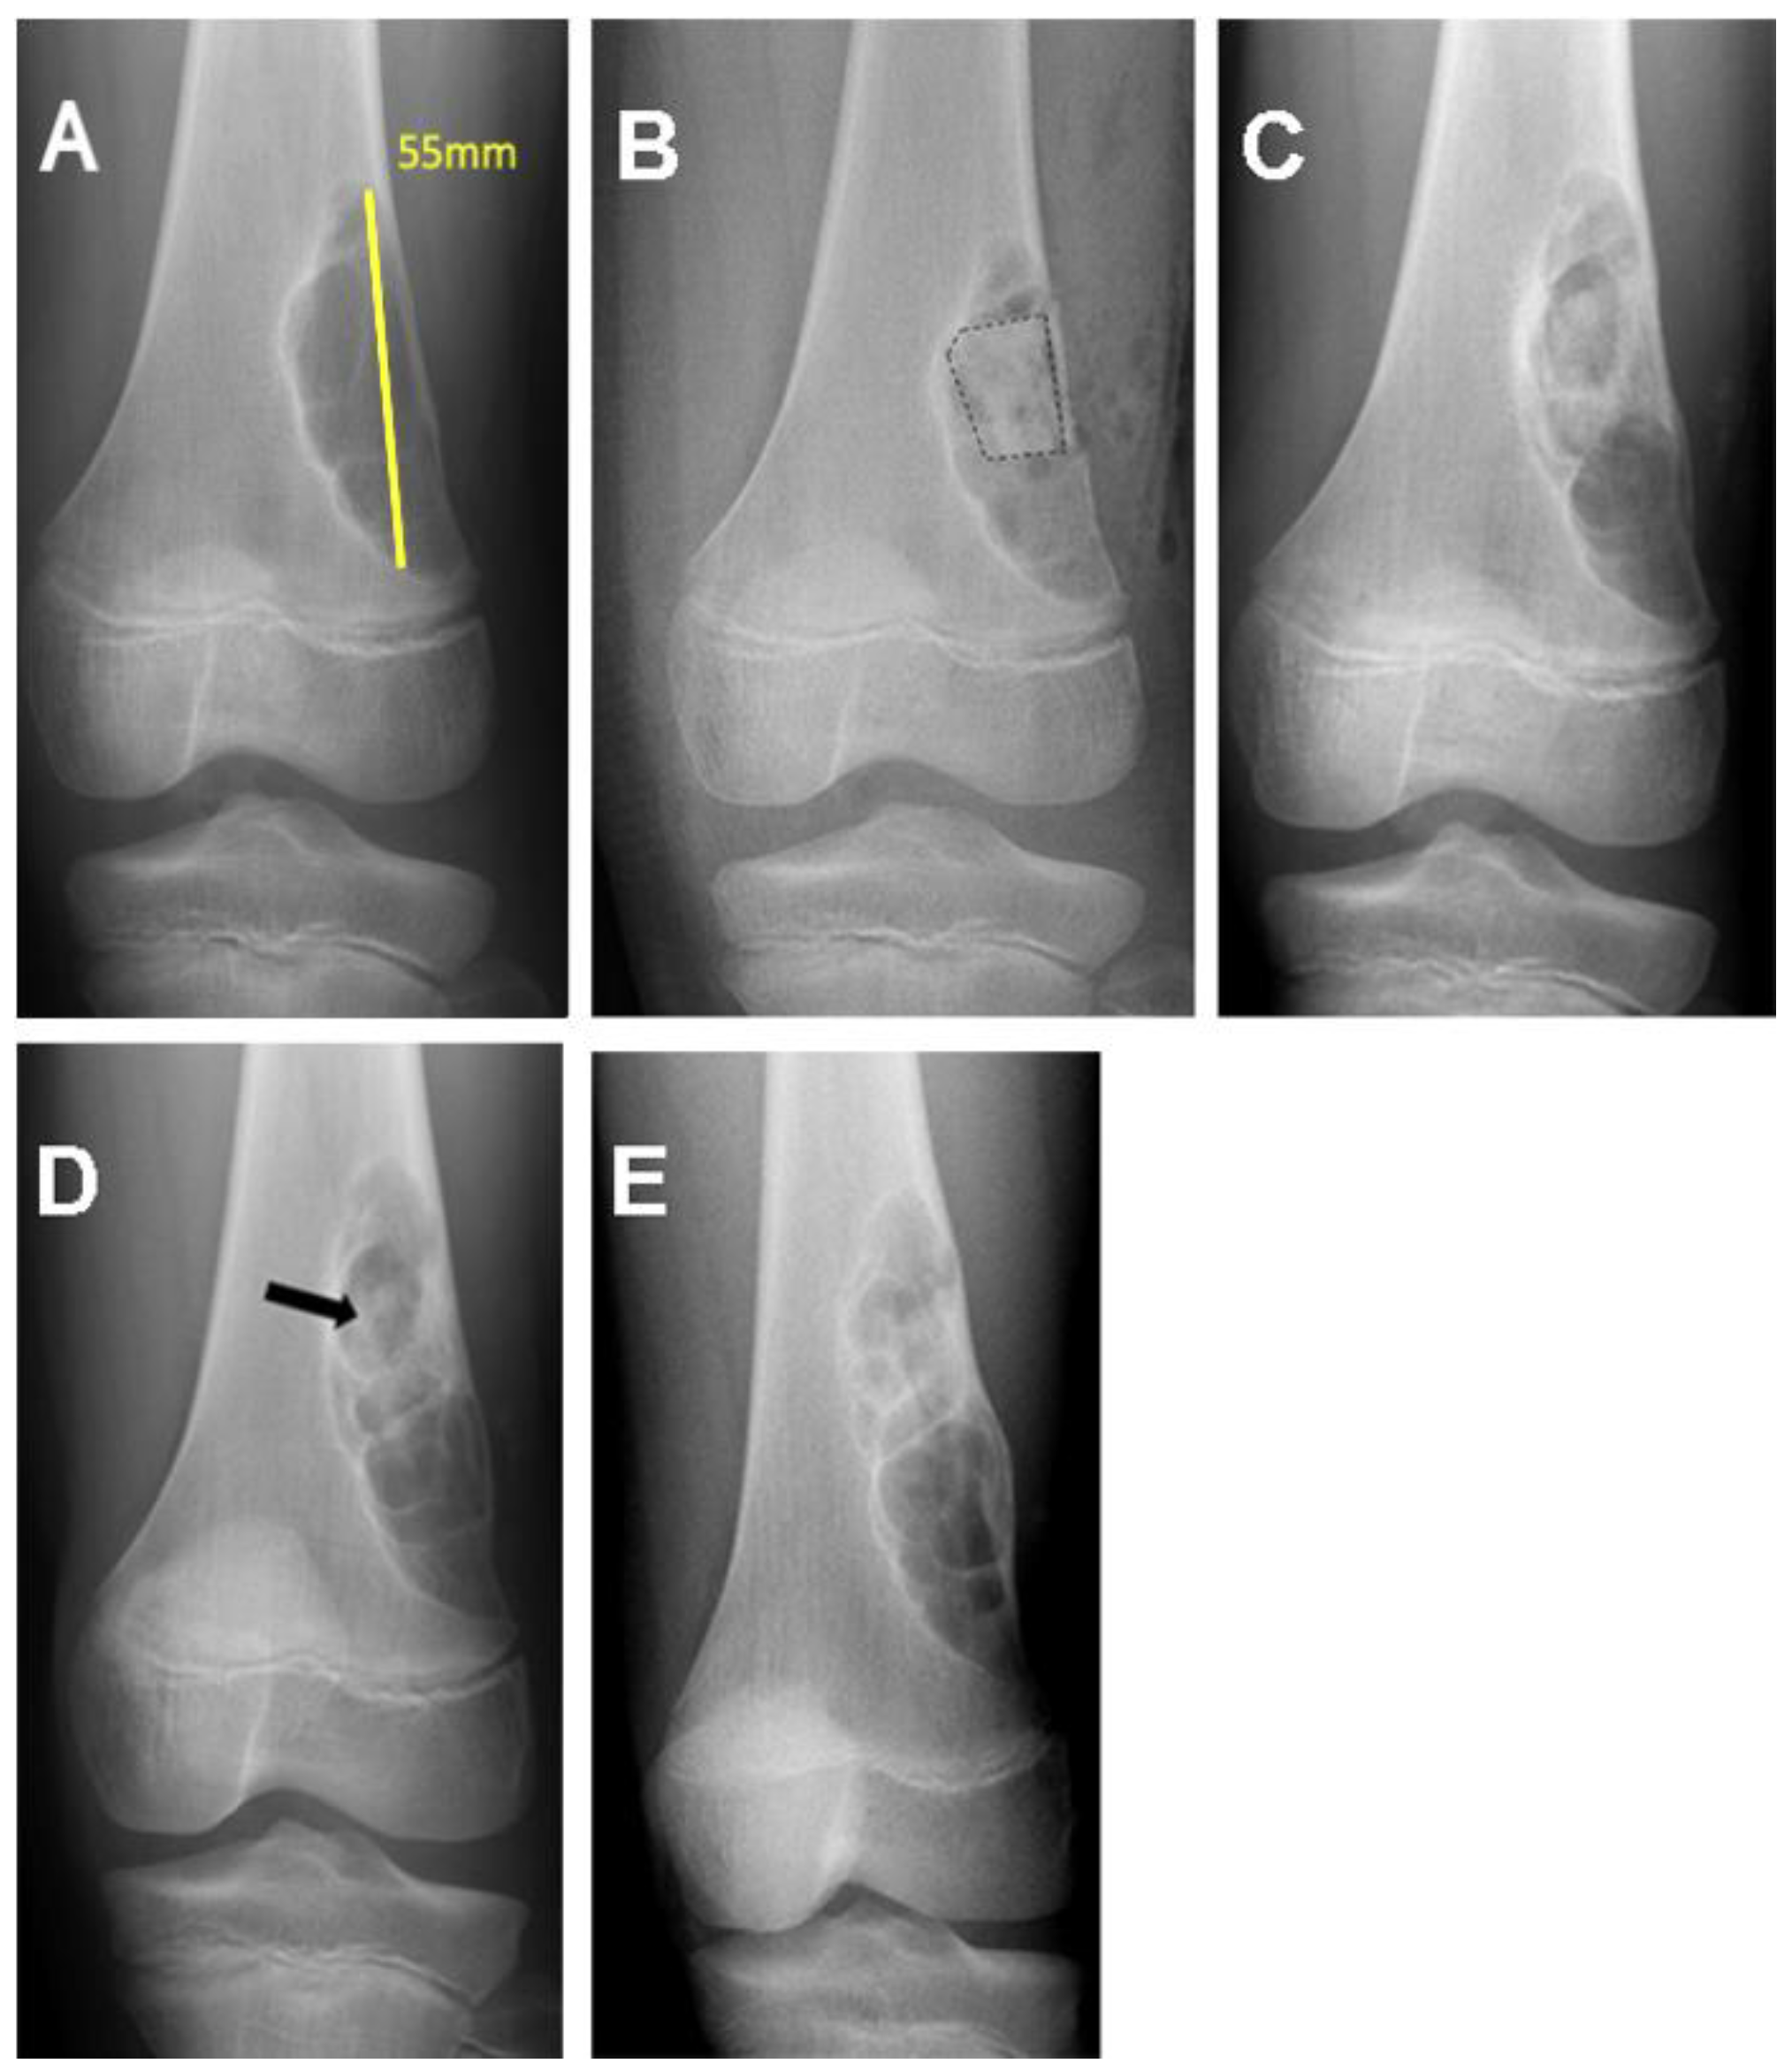

| 6/M/7 | Distal femur | Simple bone cyst | 62.96 |